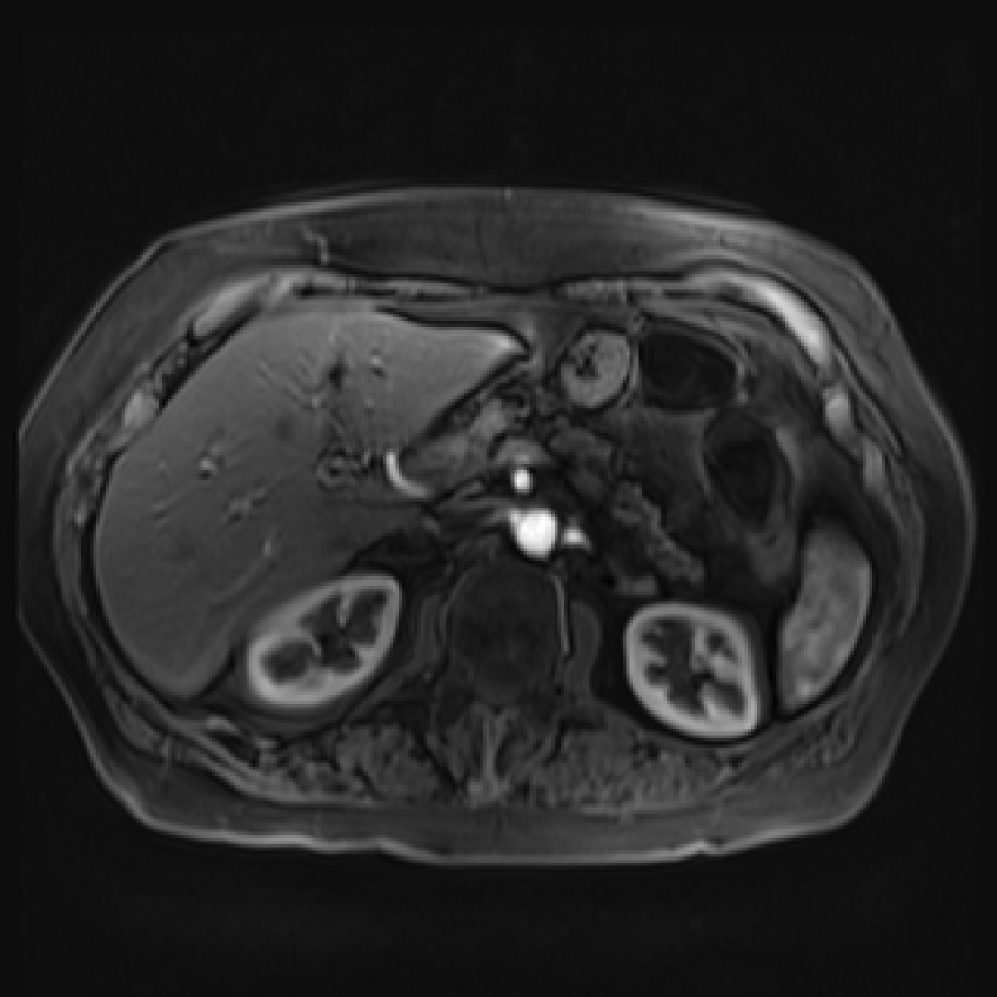

Accurate pancreas segmentation is a critical prerequisite for precise cyst analysis and classification. Recently, we developed PanSegNet [zhang2025large], a novel segmentation architecture incorporating linear self-attention layers [zhang2022dynamic] within the nnUNet framework [isensee2021nnu] to enhance global information modeling capabilities while maintaining computational efficiency (Fig. 1). PanSegNet demonstrated exceptional segmentation performance across both T1W and T2W modalities, achieving mean dice scores of 86.817.30% and 89.626.38%, respectively (Table 1, Fig. 2b-c). This performance significantly exceeded that of Swin-UNETR [hatamizadeh2021swin], one of the most used state-of-the-art transformer-based medical segmentation models, which achieved dice scores of 79.091.40% and 76.290.66% for T1W and T2W, respectively (). In this study, we integrated PanSegNet into our Cyst-X engine along with a classifier for risk prediction. In Section 2.2, we show that the choice of segmentation model affects the classification results. The performance advantage of PanSegNet was consistent across all seven medical centers, demonstrating robust generalization despite variations in imaging protocols and equipment (Table 1). This cross-institutional reliability is particularly important for clinical applications, where model performance must remain consistent regardless of imaging site or acquisition parameters.

Each patient was categorized into one of these three ground truth classes: no risk/control, IPMN low-risk, or IPMN high-risk. To evaluate variability in image acquisition, we applied uniform manifold approximation and projection (UMAP) to image quality indicators, revealing distinct clustering patterns by imaging center and slice thickness. This heterogeneity reflects real-world clinical variability, enhancing the dataset’s generalizability while presenting technical challenges for model development. Fig. 6 shows examples of low-grade, high-grade, and cancer developing IPMNs from the Cyst-X dataset.